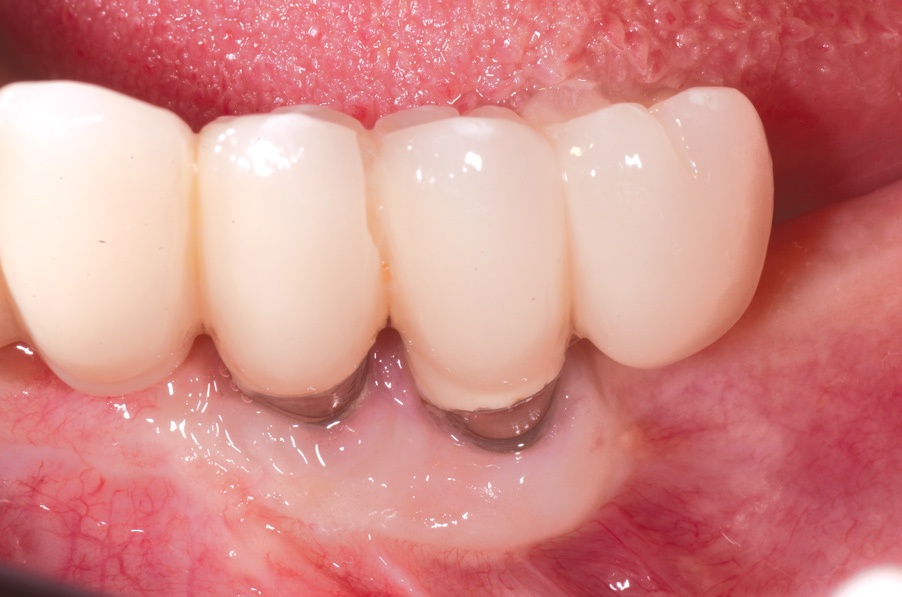

Dental implants have revolutionized the way in which clinicians treat and restore partially and fully edentulous patients and have demonstrated success for managing a broad range of clinical dilemmas. While implants have been highly predictable and have achieved long-term success, they are not immune from complications associated with improper treatment planning, poor surgical and prosthetic execution, material failure, and inadequate or infrequent maintenance. Among these problems are the biologic complications of peri-implant mucositis and peri-implantitis, which are inflammatory conditions in the soft and/or hard tissues surrounding dental implants (Figure 1 through Figure 4).1,2

A thinner gingival biotype is also a sign that the underlying bony housing may be thin; this relates to the concept of blood supply to maintain bone height. In thinner bone that is subjected to inflammation, adequate blood supply may not be present to maintain its viability. Where gingiva is thin or absent at the time of implant placement, strong consideration must be given to proactively grafting these sites with soft tissue just prior to restoration or at the earliest signs of inflammation to protect the underlying bone. Figure 8 through Figure 12 highlight such a situation.